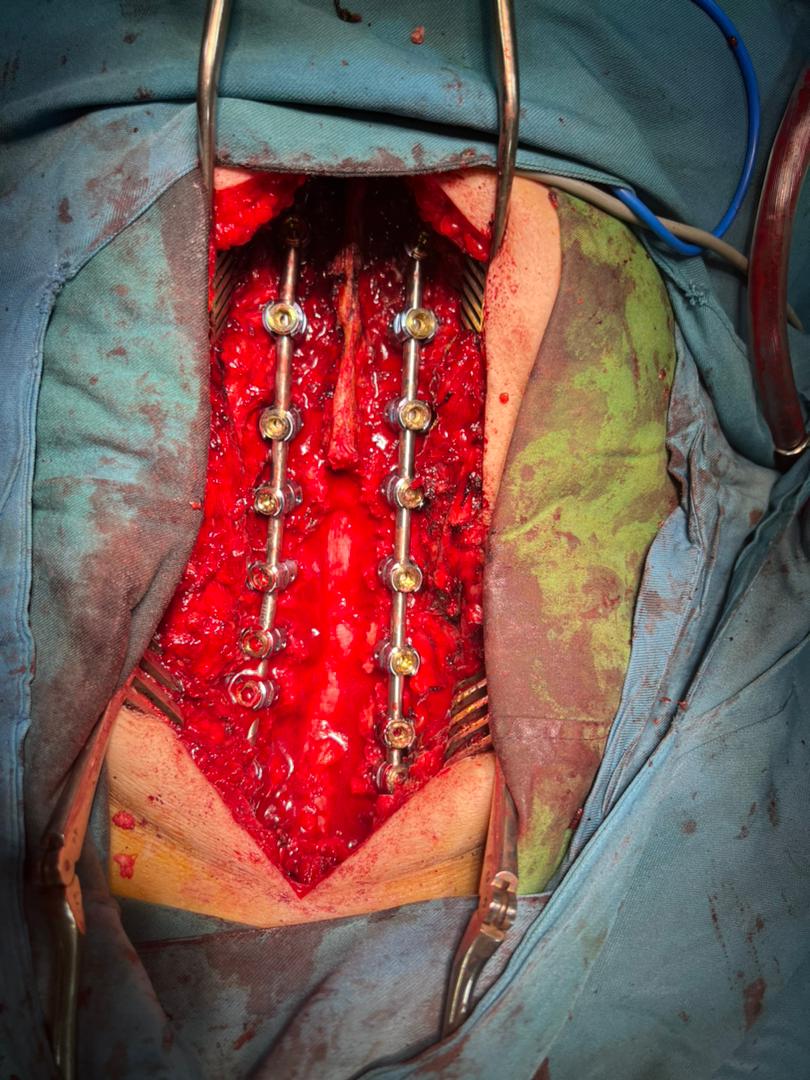

دکتر احمد جباری در توضیح عمل دوم گفت : انحراف در ستون فقرات یا اسکولیوزتوراکولومبار یعنی انحراف در وسط و پایین کمراست  که مهره ها کاملا حول محور افقی و عمودی ستون فقرات یعنی در هر دو محور پیچیده می شود و چون  اصلاح بسیار سخت و عمل ظرافت بالایی دارد جزء عمل های بسیار پیچیده ستون فقرات می باشد که شکرخدا توانستیم بدون هیچ عارضه ای در این عمل 9 مهره را پلاتین گذاری کنیم ،انحراف به وجود آمده را برطرف کرده،دردهای بیمار بهبود پیدا کرده و در نهایت عمل رضایت بخشی انجام شد.